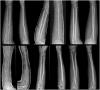

Figure 3.

Paired AP radiographs showing fracture healing in two boys aged 12, in three moments: on admission, after 3 weeks, and after 6 weeks. The first row represents a control case, and the second row represents a study case. AP: anteroposterior.